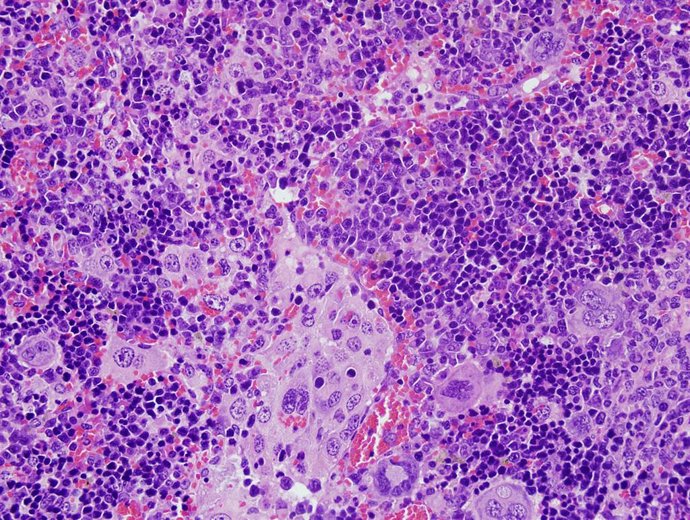

Imagen de microscopía del bazo de un ratón que ha desarrollado un linfoma periférico de células T a causa de alteraciones en el gen VAV1.

Imagen de microscopía del bazo de un ratón que ha desarrollado un linfoma periférico de células T a causa de alteraciones en el gen VAV1. - USAL

Concretamente, este grupo ha publicado un artículo científico en donde destaca la realización de un catálogo completo de las mutaciones del gen VAV1 que se habían encontrado en distintos tipos de tumores humanos y, con frecuencia más alta, en un tumor originado en células de la sangre que se conoce como linfoma periférico de células T.

En este estudio, cuyo primer firmante es el investigador del CIC y del CIBER de cáncer Javier Robles-Valero, también han demostrado que "el tipo de mutación más frecuente de VAV1 en tumores causa de forma autónoma la rápida aparición de linfomas periféricos de células T cuando se expresa en ratones".

"Junto con la demostración de que estas mutaciones de VAV1 actúan como agentes causales del cáncer, el modelo animal desarrollado en este estudio nos ha permitido desarrollar linfomas de células T que son muy similares a las que se encuentran en pacientes"; ha destacado el doctor Bustelo.